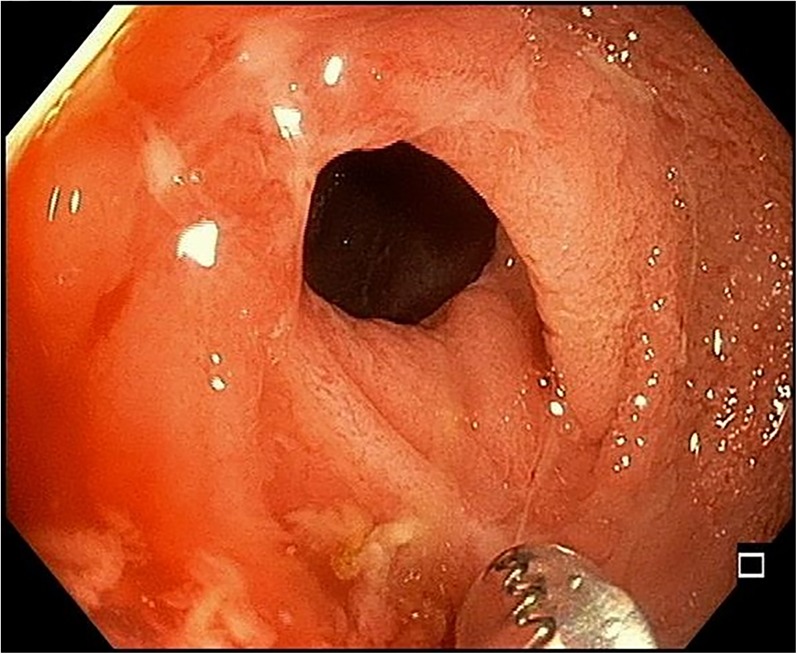

Fig. 2.

Endoscopic view of terminal ileal ulcers with luminal narrowing and stricture of the ileocecal valve, all consistent with Crohn’s ileocolitis

A 43-year-old man presented with one day of crampy, diffuse abdominal pain associated with non-bilious, non-bloody vomiting. He reported similar episodes in the past that resolved spontaneously. Physical exam revealed epigastric tenderness. Initial white blood cell count was 13,700/mm3 and the serum C reactive protein was 1.76 mg/dL. Computed tomography (CT) of the abdomen showed a partial small bowel obstruction, ileitis, and the “comb sign” (Fig. 1). Colonoscopy revealed terminal ileal ulcers with luminal narrowing and stricture of the ileocecal valve (Fig. 2); pathology was consistent with Crohn’s ileocolitis.

Crohn’s disease is characterized by transmural inflammation of the bowel wall, most often involving the terminal ileum and proximal colon. Active disease has been associated with hypervascularity of the mesentery, including vascular dilatation, tortuosity, and wide spacing of the vasa recta that resemble the teeth of a comb.1 The comb sign is not pathognomonic for Crohn’s disease, and may be seen in vasculitis, mesenteric thromboembolism, and bowel strangulation.2 However, the presence of the comb sign may help identify acute inflammation in the patient with known Crohn’s disease and differentiate active Crohn’s from hypovascular diseases such as lymphoma.1 The patient’s symptoms resolved with steroid administration.